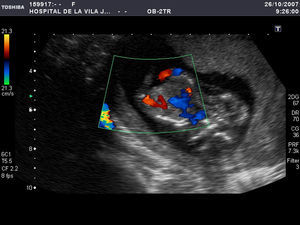

En la ecografía practicada por vía abdominal (fig. 1) se evidenció una gestación gemelar monocorial monoamniótica, en la que ambos fetos se encontraban unidos por el tórax y la parte superior del abdomen. Mostraban separación total de las cabezas, que estaban situadas cara a cara, y se visualizaban las columnas vertebrales y las cuatro extremidades en ambos fetos. Al estudiar la cavidad torácica compartida se identificó un corazón único, con latido cardíaco positivo. En el abdomen sólo fue visible un estómago en la gemela situada en el lado izquierdo y una vesícula biliar situada en la gemela derecha. Mediante Doppler color (fig. 2) se identificó la aorta en cada uno de los fetos y una única arteria renal en cada gemela. En una de las gemelas estaban presentes ambas arterias umbilicales, mientras que en la otra sólo era visible una de ellas. CRL=65,4mm. La translucencia nucal en una de las gemelas era de 5,6mm y en la otra de 5,8mm. Se practicó una ecografía 3D que confirmó el diagnóstico y fue muy ilustrativa para los padres. Informados acerca del mal pronóstico, los padres decidieron interrumpir la gestación. Tras la administración de prostaglandinas intravaginales, la paciente expulsó en bloque los dos fetos fusionados y la placenta. Posteriormente, se practicó un legrado ante la persistencia de restos y se administró gamma-globulina Anti-D, ya que la paciente era Rh negativa.

El pronóstico más ominoso es el de los siameses que comparten el hígado, el corazón o ambos7. Los siameses toracoabdominopagos comparten el hígado en todos los casos, el pericardio en el 90% y el corazón en un 75%3. Lechman et al han identificado tres tipos de unión cardíaca: el tipo A (un saco pericárdico común con dos corazones completamente separados), el tipo B (un saco pericárdico común con comunicaciones auriculares solamente) y el tipo C (un saco pericárdico común con interconexiones auriculares y ventriculares). Chin revisó 47 casos de siameses toracoabdominopagos que fueron separados quirúrgicamente y los resultados fueron los siguientes: el 70% con unión cardíaca tipo A sobrevivió, el 10% con la unión tipo B y el 0% con la tipo C2. Por tanto, en el caso de los siameses toracoabdominopagos es muy importante investigar la anatomía cardiovascular, ya que de ella dependen el pronóstico y las opciones de tratamiento2,3. El uso del Doppler color puede ser útil, ya que ayuda a determinar las estructuras vasculares compartidas2,3,9. La capacidad del Doppler color para detectar el flujo de sangre sincrónico en ambos arcos aórticos incrementa la seguridad diagnóstica de siameses con un corazón fusionado2.